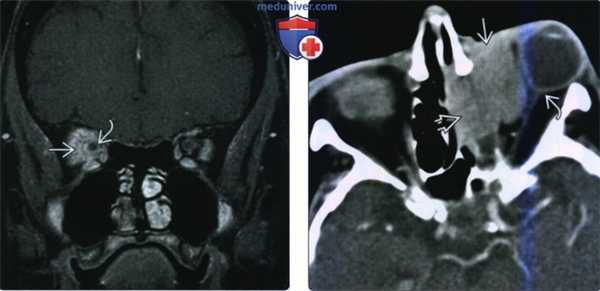

(Слева) При аксиальной МРТ Т1 ВИ FS с КУ определяется утолщение хориоидеи заднего отрезка левого глазного яблока и распространение опухоли через верхнюю глазничную щель в кавернозный синус. Из-за большого объема экстраокулярного поражения и обширной опухолевой инфильтрации этот случай не типичен.

(Справа) При МРТ Т2 ВИ в аксиальной проекции регистрируется характерный низкий Т2 сигнал как внутриглазного, так и экстраокуляр-ного компонентов инфильтративного новообразования, что подтверждает диагноз меланомы глаза.